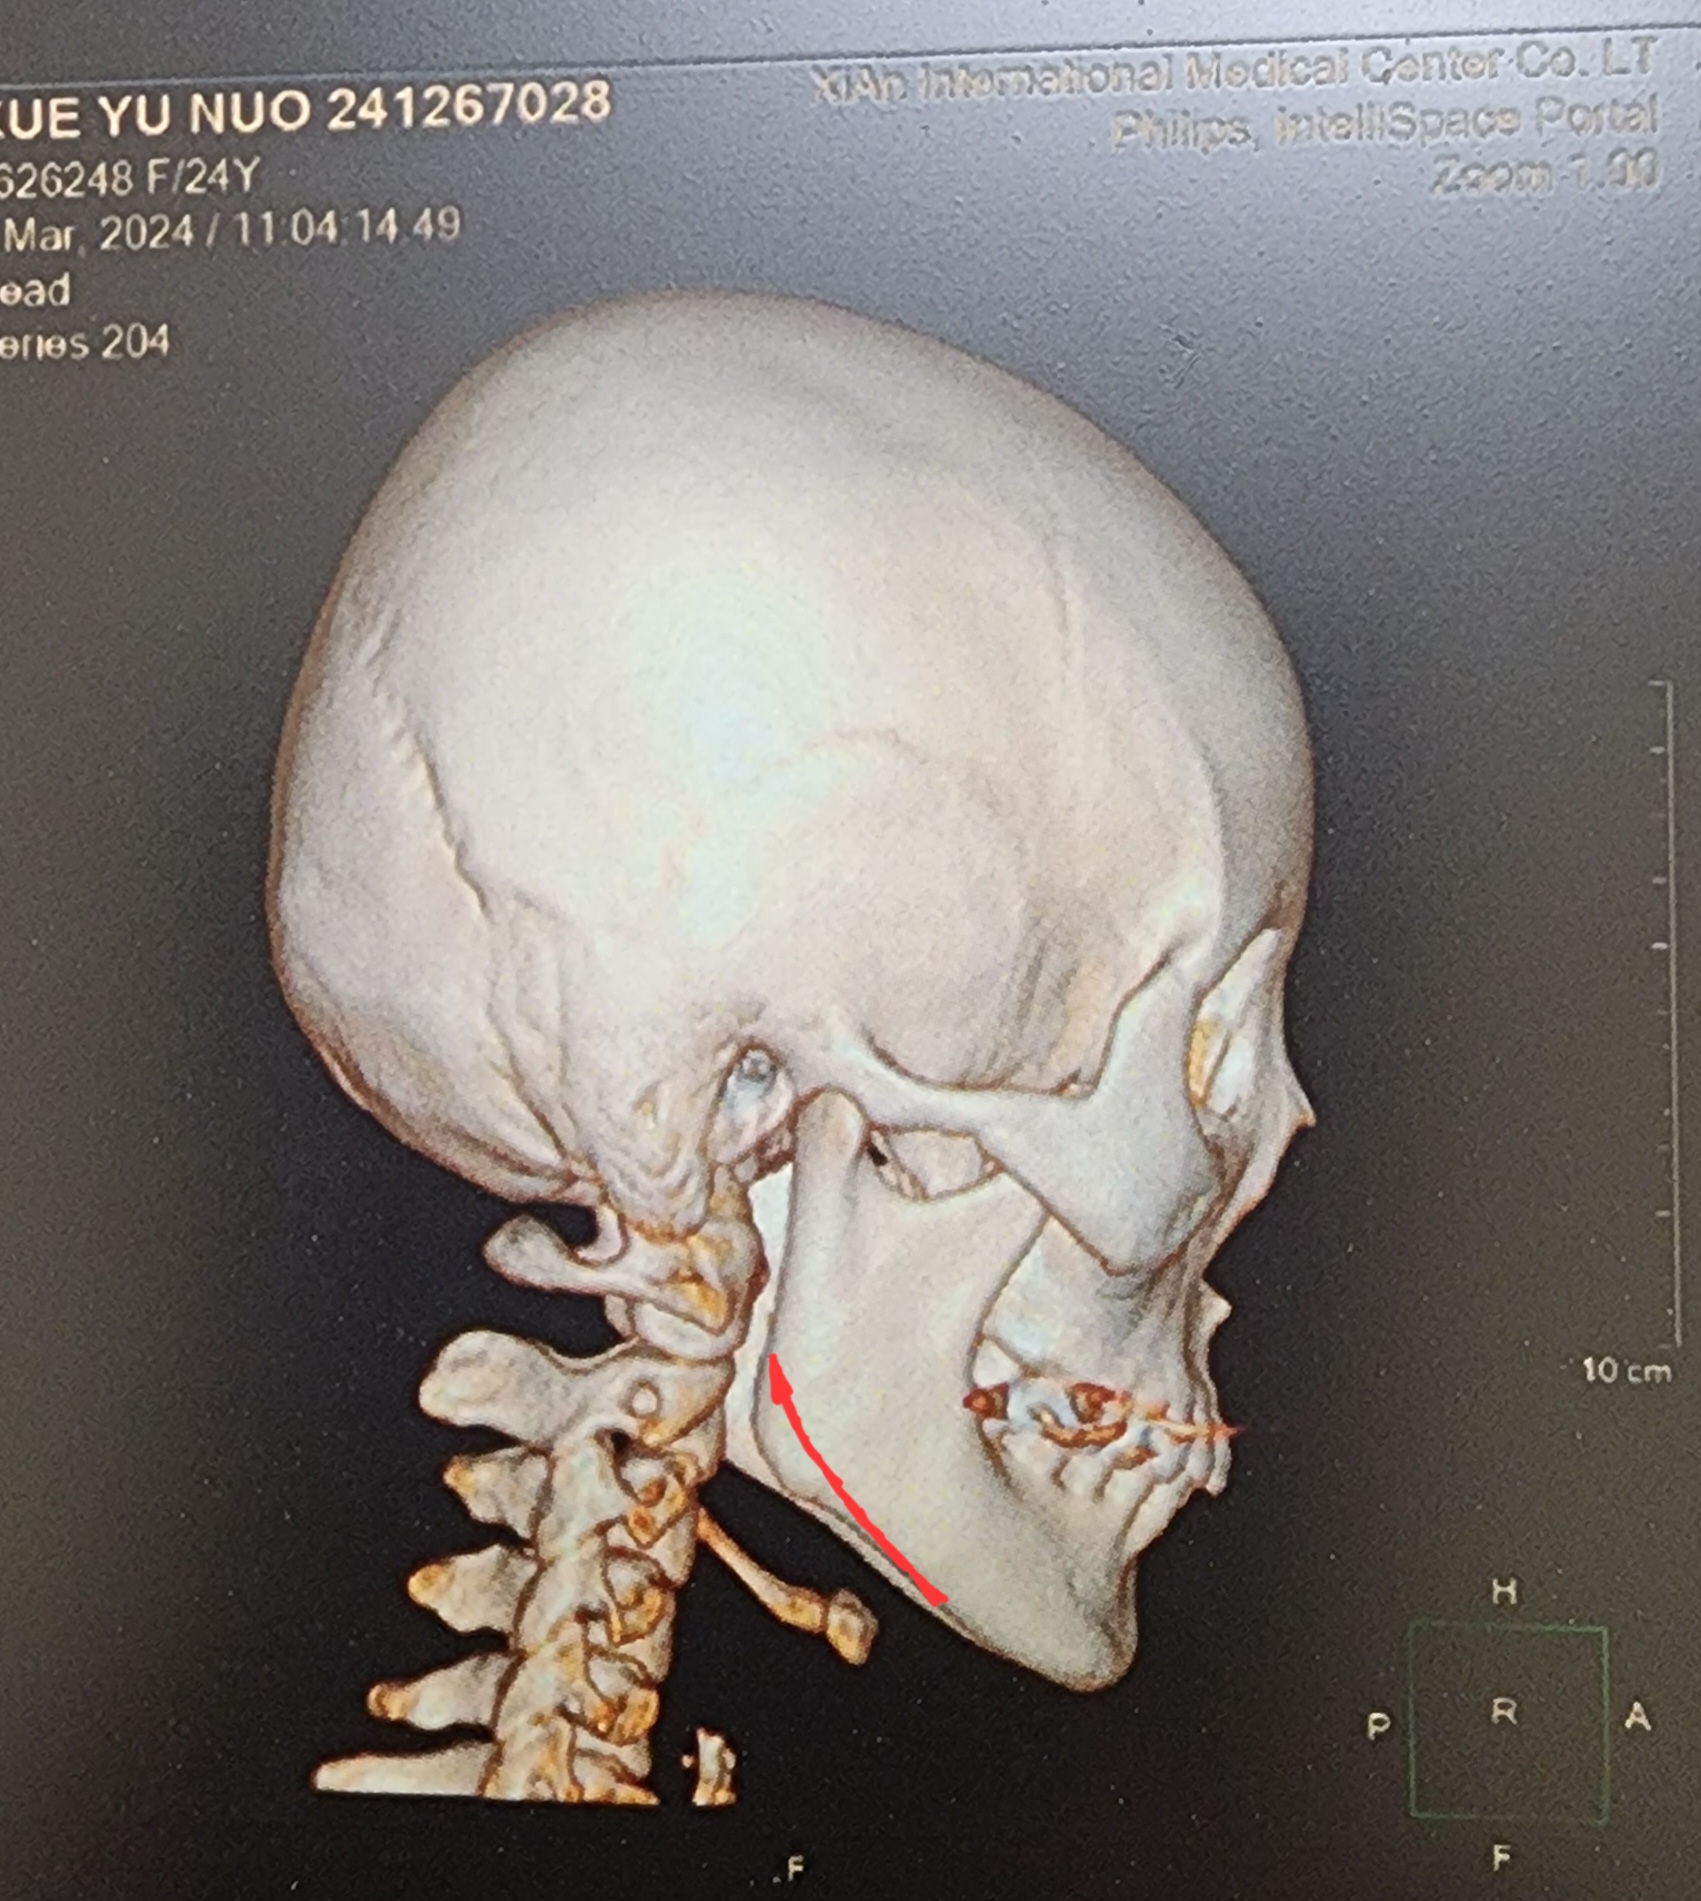

偏颌畸形

正颌偏颌牙片

偏颌反颌无法和解